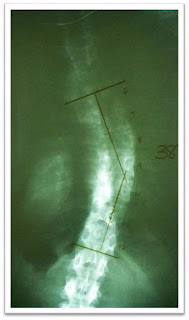

For YEARS I drowned myself in massively

over-sized tops to hide a 42.5 degree curve in my spine; a curve that caused my

So far my curve has been reduced from 42.5 degrees to 38 degrees.

I've also had a reduction in my rib hump; I’m able to wear clothes that I never would have